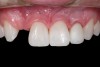

Fig 4. Double-wing metal resin-bonded (Maryland) bridge replacing the right lateral incisor (facial view).

Figure 4

Once the teeth were bonded to ideal size, the "Maryland Bridge" was fabricated from a polyvinyl arch impression with the newly bonded teeth (Figure 3). The metal frame was cast from a non-precious alloy to allow for fabrication of a very thin frame and to create a better surface for bonding. After sandblasting the internal aspect of the frame with CoJet silica (3M ESPE), accomplishing salinization, and executing cementation with a dual-cure resin cement, a fairly good adhesion to the frame was anticipated.29 The enamel surface was etched with phosphoric acid for 30 seconds, the primer (Single Bond Plus, 3M ESPE) was applied to both the internal surface of the sandblasted framework and the etched enamel, and the bridge was cemented with RelyX ARC (3M Espe) dual-cured resin cement (Figure 4 and Figure 5).